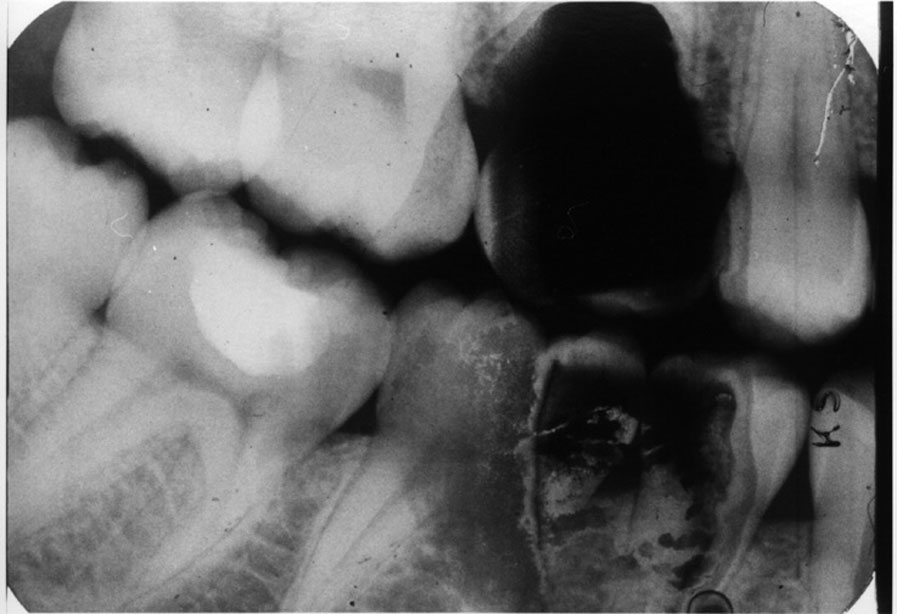

Double Exposure

Description: Double exposures occur when the same film is used for more than one exposure (Figure 1). This can occur if the operator confuses an exposed film with an unexposed film and places the packet into the patient’s mouth as if it were unused. Double exposures can also result from activating the exposure button twice.

Differential Diagnosis: The resulting film is dark because it has technically been overexposed, resulting in confusing, overlapped anatomic images.

Consequences: Retakes are almost always necessary because of the lost detail caused by anatomic superimpositions. Fortunately, double use of a packet usually occurs with the same patient in the chair; but if a previously exposed film from one patient were placed into the mouth of another, the operator would be running the risk of cross-contamination and transmitting disease between patients.

Remedy: After a film packet has been exposed the op­erator should place the film into a lead receptacle. Unexposed films and exposed films should never be kept in the same area.

Figure 1. Double exposure.

Figure 1